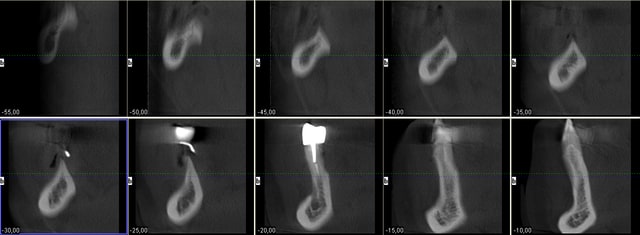

Au maxillaire il faut faire une implanto totale et stt ne pas garder les canines

A la mandibule faut disker mais ça va

PS il faut d abord faire réaliser des modèles stéréolithographiques par Materialise pour se prononcer au final

Je rentre cette apm et je tente de charger ton examen cone beam

Pcq ds ces cas là onne sait pas faire autrement

1. les palques ont une assisse énorme par rapport à 7 cylindres

2. la résorption centripède du maxillaire le rend trop petit pour en poser plus

De plus malgré le grand overjet , on a qd même un implant central qui soutient l arc incisif, même s il est 2 cm en arrière de la ligne des dents